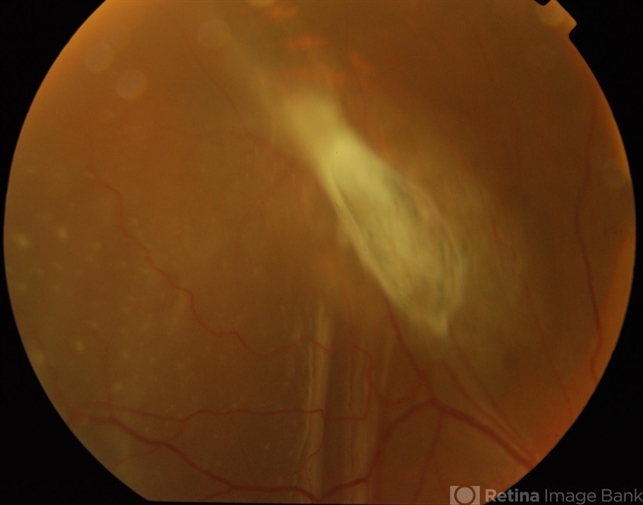

- detachment

- Male patient, 25-years-old had a complaint of difficulty in vision and pain with watering and itching. On examination his vision of the right eye was normal and left eye is 6/9. It seems to be a case of retinal detachment.